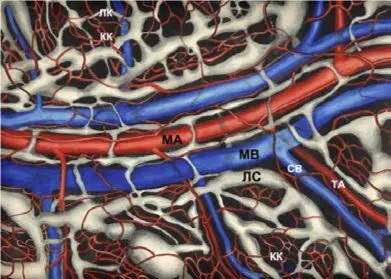

Ангиоархитектоника микроциркуляторного русла брыжейки тонкой кишки: МА, МВ – магистральные артериола и две венулы в одном пучке; ЛС – лимфатический сосуд; ТА – терминальная артериола; СВ – собирательная венула; ЛК и КК – лимфатические и кровеносные капилляры